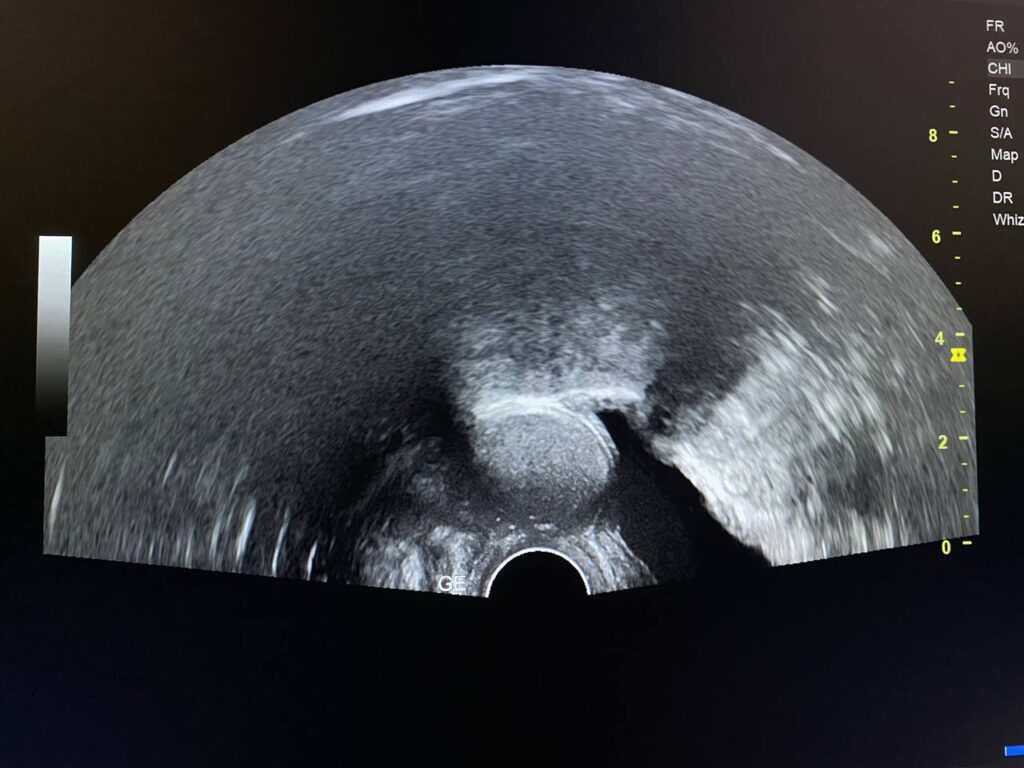

presence of well defined avascular heterogenous cystic mass 26x21mm , between the corpocervical junction and posterior urinary bladder , mostly endometriosis

presence of well defined avascular heterogenous cystic mass 26x21mm , between the corpocervical junction and posterior urinary bladder , mostly endometriosis